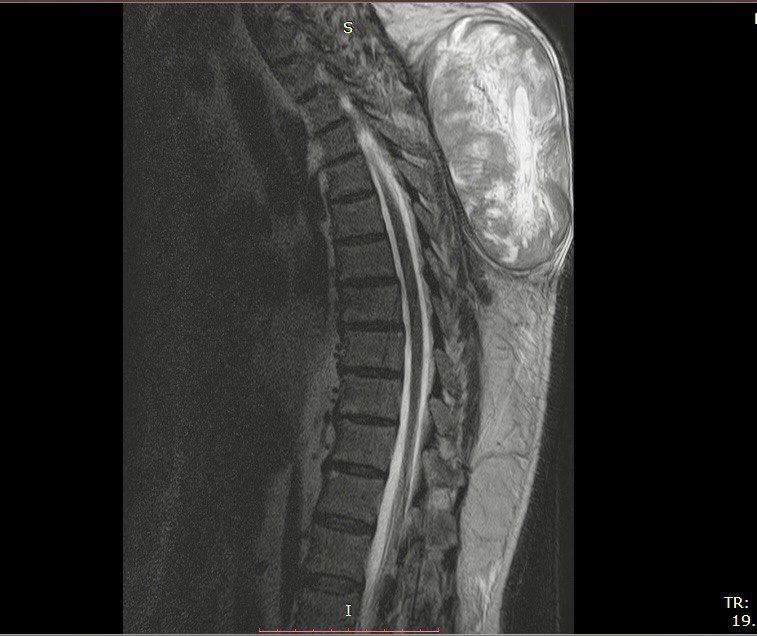

В больницу поступил 60-летний туляк для оперативного лечения гигантской опухоли грудного отдела позвоночника. Он жил с образованием с 2023 года, она стремительно росла и за несколько месяцев в несколько раз увеличилась в размерах.

Мужчина не раз консультировался у врачей Москвы и Тулы. Опухоль причиняла боль и дискомфорт. Также она вызвала грубое сдавливание мягких тканей и нарушения питания тканей. Медики провели пациенту МРТ, УЗИ и биопсию, после чего его подготовили к операции.

Операция шла больше 4 часов. По словам заведующего нейрохирургического отделения спинно-мозговой травмы Андрея Хохлова, опухоль была размером более 35 см и весом 4,5 кг. Ее успешно удалили благодаря современной аппаратуре, которая свела к минимуму кровопотерю. Пациенту провели пластику кожных покровов, чтобы рана быстрее зажила.